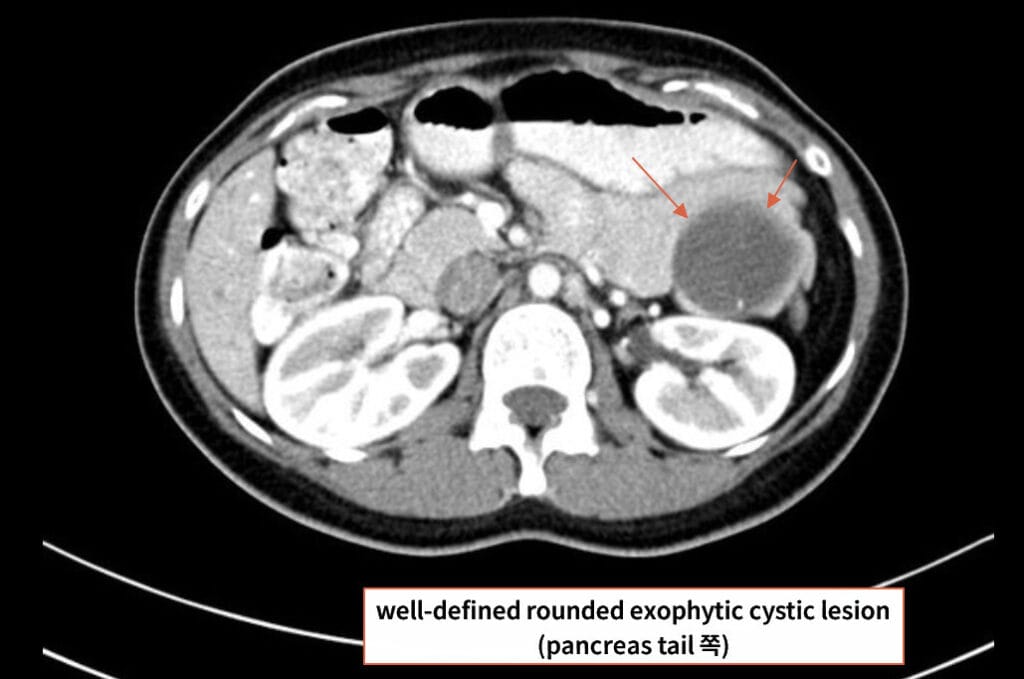

영상 소견

췌장 체부/미부에 단일성, 격벽성 낭종으로 나타나며, 췌관과 연결되지 않습니다.

| 🟦 Unilocular or septated cyst in pancreatic body/tail |

| 단일성 또는 격벽성 낭종이며, 주변 장기로 압박을 줄 수 있습니다. |

| 🟦 No communication with pancreatic duct |

| IPMN과 달리 췌관과 연결되지 않습니다. |